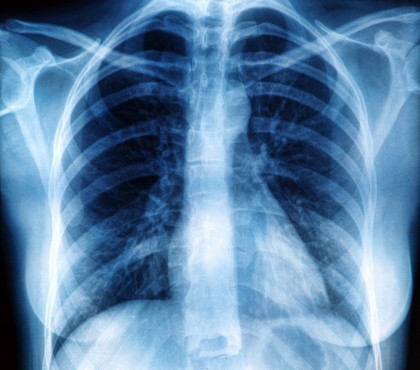

Tratarea cancerului bronho-pulmonar fără celule mici atunci când radioterapia eșuează

Cancerul pulmonar este în prezent cel mai frecvent cancer din lume, cu 2,2 milioane de cazuri noi anual. Este încă o patologie gravă, cu o rată a mortalității crescută în ciuda strategiilor terapeutice dezvoltate și a cunoștințelor acumulate în ultimii ani. Sunt necesare noi metode de tratament pentru abordul corespunzător al tumorilor pulmonare aflate în stadiu avansat, când opțiunile terapeutice sunt destul de limitate.

În cancerul bronho-pulmonar fără celule mici, radioterapia este adeseori ineficientă din cauza unor mutații genetice. Gena PTEN interacționează cu enzima de reparare a ADN-ului, fiind un biomarker ideal, conform cercetătorilor.

Tumorile pulmonare care au rezistență la radioterapie prin această mutație, pot fi tratate prin blocarea enzimei de reparare a ADN-ului, cu ajutorul a doi inhibitori aflați în studii clinice. Astfel, tumorile devin din nou sensibile la radioterapie.

Studiul publicat în revista Cell and Bioscience oferă posibilitatea de a identifica rapid pacienții cu cancer bronho-pulmonar fără celule mici, care suferă de mutația PTEN și prezintă rezistență la radioterapie.